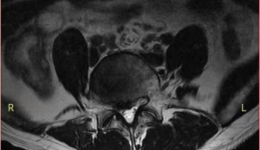

• 腿痛难行病在腰  微创镜下解顽疾 —毕节市三医“椎间孔镜微创手术”

腿痛难行病在腰 微创镜下解顽疾 —毕节市三医“椎间孔镜微创手术”